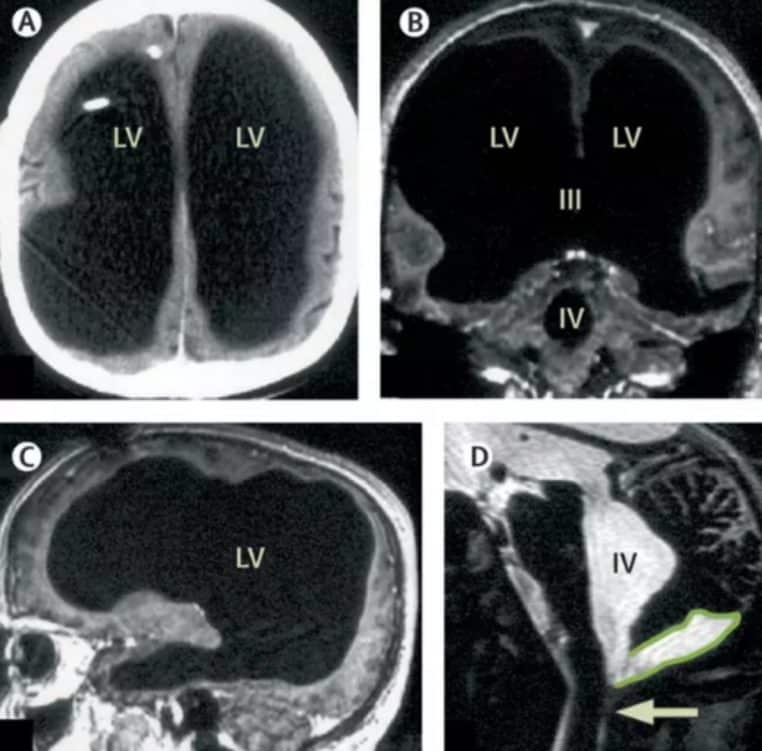

Ce cas remet en cause de nombreuses certitudes scientifiques liées au cerveau humain. En effet, les spécialistes ne comprennent pas comme ce Français a pu vivre une vie normale en ayant un cerveau à 10% de ses capacités réelles. C’est d’ailleurs lors d’une IRM que les scanners ont montré que la majeure partie de son crâne a été remplacée par un liquide.

Au fil du temps, le tissu cérébral a été comprimé au bord de son crâne, laissant le liquide prendre de plus en plus de place. Mais ce liquide n’est pas anodin. C’est le résultat d’une affection appelée « hydrocéphalie » . Malgré tout, l’homme a vécu une vie normale, et n’est pas en situation de handicap.